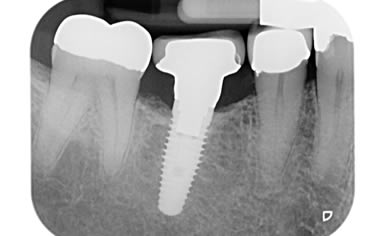

More back teeth replaced by dental implants

Case Four (4 images)